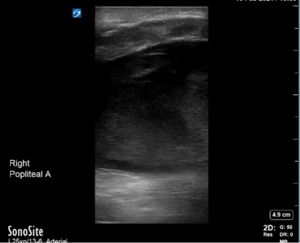

Bedside ultrasonography confirmed a large hematoma with heterogeneity in the popliteal fossa extending superiorly into the distal femur and inferiorly into the calf. While the femoral artery was found without anomalies on ultrasound, no popliteal artery could be found in the popliteal hematoma (Figures 3 and 4). This was concerning for active bleeding in the popliteal fossa from damage to the artery.